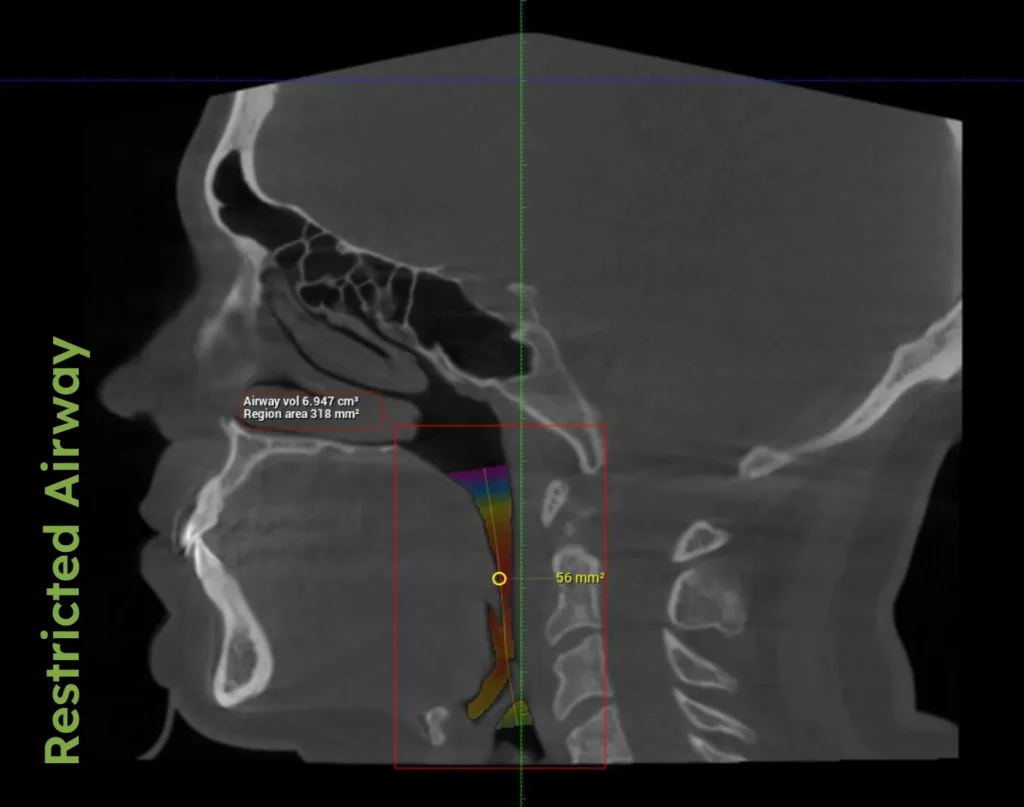

In his book AIM, Dr. Porter explains how traditional orthodontics, primarily focused on straightening teeth, often overlooks the critical aspect of airway health. Conventional orthodontic approaches can pull the front teeth backward, inadvertently narrowing the airway and leading to problems such as habitual mouth breathing and snoring—both clear indicators of potential airway compromises.

Adults with airway problems may experience chronic snoring, daytime sleepiness, or difficulty breathing at night. These symptoms necessitate comprehensive evaluations to manage and treat underlying airway issues effectively.